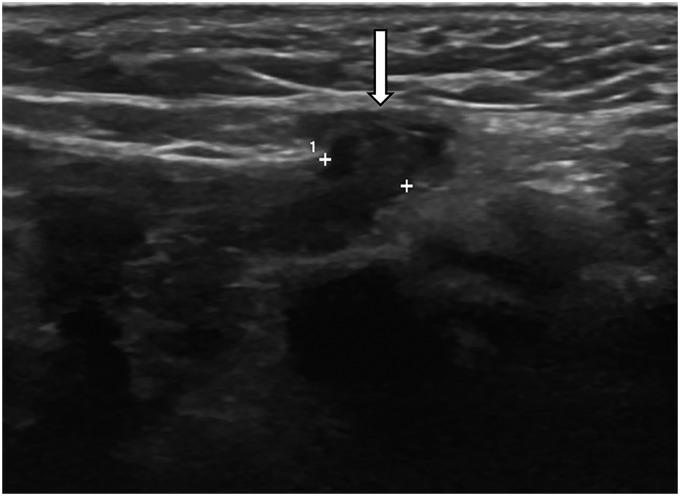

The canal of Nuck, caused by the failed closure of the processus vaginalis in the female, is the continued outpouching of parietal peritoneum through the inguinal canal to the labia majora. Disorders of the canal of Nuck include hernia and hydrocele. Some canal of Nuck hernias, especially of the ovary, may result in emergent complications such as incarceration, strangulation, and ovarian torsion. Knowledge of canal of Nuck disorders and prompt diagnosis are important to avoid serious complications. Imaging, especially ultrasound, is essential for timely diagnosis, leading to appropriate management and better patient care.

女性的努克管是由鞘突未闭引起的,是壁层腹膜经腹股沟管持续向外突出至大阴唇。努克管疾病包括疝和鞘膜积液。一些努克管疝,尤其是卵巢疝,可能导致诸如嵌顿、绞窄和卵巢扭转等紧急并发症。了解努克管疾病并及时诊断对于避免严重并发症很重要。影像学检查,尤其是超声检查,对于及时诊断至关重要,可据此进行适当的治疗并为患者提供更好的护理。